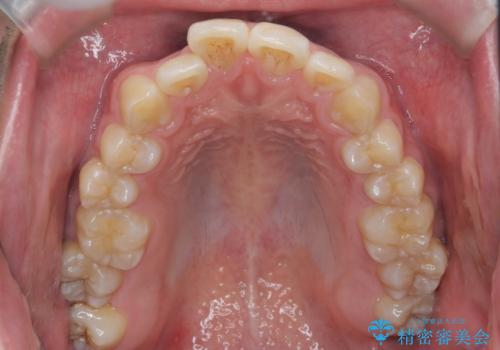

マウスピース矯正で前歯の角度、ガタガタをきれいに

- 突き出た前歯の角度、歯ブラシのしづらい前歯のがたつきの改善を希望され来院されました。

4本の小臼歯を抜きワイヤー矯正治療、下顎前歯を1本抜去しマウスピース治療のメリットデメリットを検討・相談し、より歯を抜く本数の少ないマウスピース矯正を行うこととなりました。

下顎の前歯は1本だけ抜去せざるをえませんでしたが、4本の小臼歯抜去とマルチブラケット矯正を回避することができ、治療結果・過程に満足いただくことができました。